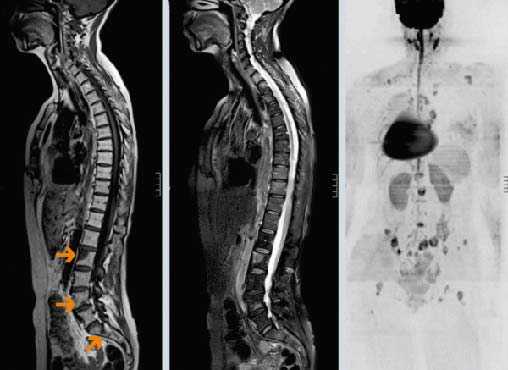

По данным МРТ пояснично-крестцового отдела позвоночника от 14.09.14 в позвонках Th11-S1 визуализируются множественные метастазы различных размеров (вплоть до тотального поражения позвонка). Данные изменения распространяются на дужку и отростки L1 позвонка с их расширением и деформацией, с выраженным перифокальным отёком паравертебральных мягких тканей и муфтообразным сужением позвоночного канала на данном уровне на 79% — до 0,3 см. Элементы конского хвоста компремированы и деформированы на данном уровне (рисунок № 3).

По данным МРТ от 06.12.14 в сравнении с данными исследования от 14.09.14 отмечается уменьшение размеров внекостного компонента в области L1 позвонка и уменьшение степени стеноза позвоночного канала на этом уровне (просвет спинномозгового канала увеличился с 0,3 до 0,6 см). Участки поражения в позвонках приобрели более чёткие контуры, в их структуре нарос компонент с низким сигналом во всех режимах исследования (пластический компонент — частичная репарация), уменьшилась интенсивность перифокального отёка костного мозга и паравертебральных мягких тканей на уровне L1 позвонка (рисунок № 4).